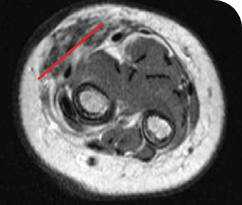

Reduction in tumor burden1

MRIa imagery of the brain. Red line indicates the maximum dimension.1

aMRI, magnetic resonance imaging.

Pre- and post-treatment imaging, by DuBois SG et al, is licensed under CC BY 4.0.